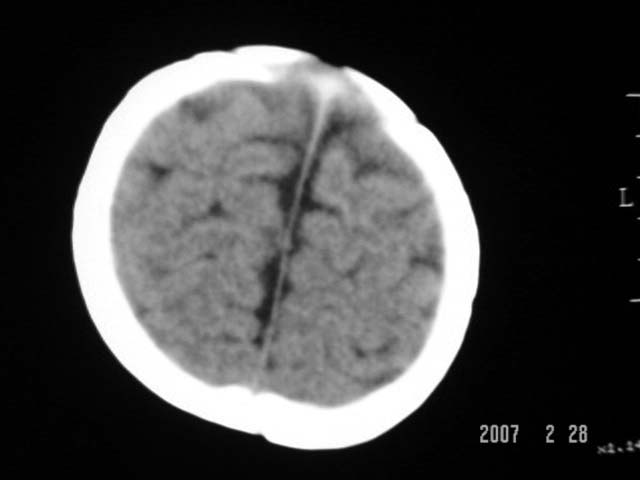

标题: PED0015:男,8M,发现不会坐立及神情异常,前囟已闭,双眼斜视, [打印本页]

标题: PED0015:男,8M,发现不会坐立及神情异常,前囟已闭,双眼斜视,

脑回较深,白质范围小,灰白质比例失调。余未见明显异常。

考虑:脑白质发育不良,必要时请做mri进一步检查。